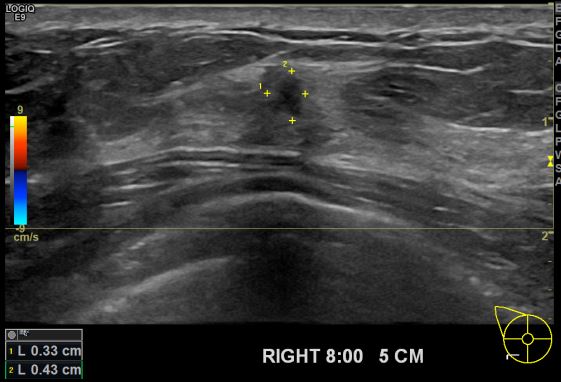

건강검진상 이상소견으로 내원하신 40대 여성분으로 본원 초음파상 우측 8시 방향

5cm 떨어진 거리에 의심스러운 멍울 조직검사 시행하여 우측 침윤성 윤관암 진단 되었습니다.